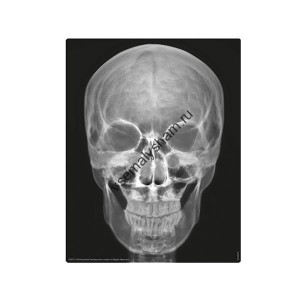

- Код артикула: 00-03375С данным набором ребенок сделает из гипса достоверную модель человеческого скелета. Каждая косточка отливается из гипса отдельно. Затем высохшие детали соединяются вместе по схеме. Собирая скелет, дети лучше всего запоминают его строение и понимают, насколько продуман и интересен человеческий организм.

- Код артикула: 00-03374Набор принесет больше всего пользы, если в сборке моделей будут участвовать родители. Таким образом, удастся преодолеть все сложные моменты и поговорить о строении человека. Необходимую информацию вы найдете в инструкции на русском языке, в которой указаны все этапы работы с набором.